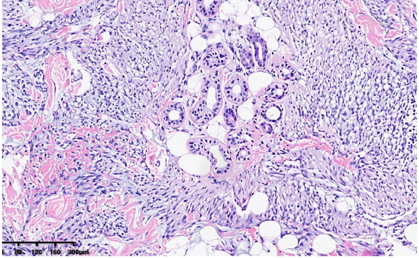

低倍镜下,肿瘤位于真皮层及皮下,肿瘤主要由梭形细胞构成,含有少量卵圆形细胞,部分区细胞丰富,部分区细胞较稀疏,梭形细胞排列成编织状、束状及旋涡状(图1A)。肿瘤细胞与周围组织呈交错浸润性生长,局部呈膨胀性/推挤性生长。肿瘤内薄壁血管较丰富,呈分支状,管腔开放,局部可见少量淋巴细胞浸润(图1B)。肿瘤细胞累及脂肪及皮肤附属器,部分区间质可见黏液水肿/变性及纤维胶原增生(图1C)。

高倍镜下,细胞核呈长/短梭形或卵圆形,染色质细腻/开放,核膜光滑,可见细小核仁。胞浆嗜伊红,较丰富,核浆比尚可。偶见多形性细胞和多核细胞,偶可见核分裂象(热点区约1个/10HPF)(图1D),未见肿瘤性坏死及病理性核分裂。根据FNCLCC分级,肿瘤细胞的形态符合低级别。

肿瘤细胞S-100(核浆+),CD34(+),ALK 1A4(+),ALK(Ventana-D5F3)(+),SMA部分(+)(图2A、图2B、图2C、图2D),Ki-67热点区(5%+);pan-TRK(roche)(-),SOX-10、EMA、STAT-6、Desmin、HMB45、AE1/AE3均为阴性;H3K27me3、INI-1未缺失;P53野生型。

组织形态学上,5例局限于真皮,3例肿瘤主体位于皮下(真皮深层受累有限)。肿瘤细胞由梭形细胞及卵圆形细胞组成,交叉、束状生长或无规律排列;大部分肿瘤细胞异型性小,染色质细腻,细胞质轻-中度嗜酸性,细胞边界不清;这部分肿瘤细胞形态温和,核分裂少见(<1个/10 HPF),符合低级别肿瘤形态。部分区间质胶原化及黏液变性,肿瘤含有线性-分支状薄壁血管,肿瘤周边呈浸润性/交错性边界。部分肿瘤细胞可呈上皮样形态,个别病例表现出肿瘤细胞核局灶的多形性,肿瘤性坏死范围不等,一般较少见;然而,也有少量区域可表现为核分裂象活跃及灶性坏死,形态学符合中级别肉瘤[1]。大部分肿瘤伴有少-中等量淋巴细胞浸润,也可见弥漫散在的淋巴细胞浸润/积聚,类似炎症性肌纤维母细胞瘤(IMT)。肿瘤细胞均显示出免疫组化弥漫性ALK(D5F3克隆)的阳性表达。其中7例弥漫性共表达CD34和S100蛋白,另外1例只表达CD34,但不表达S100蛋白。所有病例的肿瘤细胞EMA、AE1/AE3、和SOX10均为阴性。分子检测中,通过一代测序(NGS)及RT-PCR(ARMS方法)检测到PLEKHH2:ALK融合或EML4:ALK融合[1]。文献中的病例与本例形态学及分子改变具有高度重叠性。